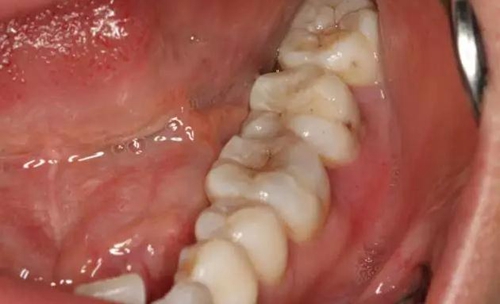

圖1.患者自述右側(cè)下后牙牙齦紅腫,咀嚼不適。術(shù)前口內(nèi)像:37頰側(cè)牙齦紅腫

10.jpg